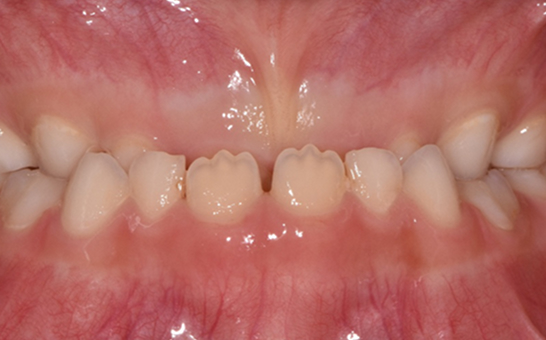

인비절라인 퍼스트(Invisalign First)는 어린이와

성장기 청소년을 위한 투명 교정 장치로, 치아와 턱뼈가

성장하는 과정에 맞춰 설계된 교정 시스템입니다.

해당하는 증상이 있다면 전문의와 상담 후 조기 교정 시

성장기 어린이에게 교합이 틀어지는것을 미리 예방 할 수 있습니다.

※ 바른선택치과의원은 의료법을 준수하며 위 케이스는 실제 내원 환자분의 동의하에 공개된 사진과 동일한 환자분께 같은 조건에서 촬영한 사진을 활용했습니다.

개인에 따라 진료 및 치료 방법이 다르게 적용할 수 있으며, 효과와 부작용이 개인마다 다르게 나타날 수 있는 점을 안내해 드리며, 진료 전 전문의료진과 충분한 상담을 권해드립니다.